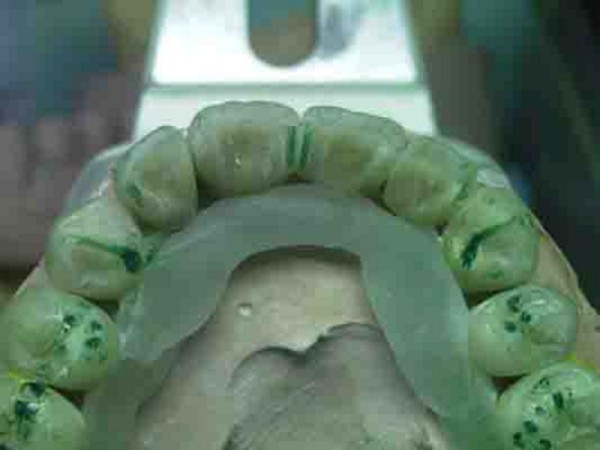

RESUMEN Es un desafío complejo conseguir una secuencia lógica de trabajo en la reconstrucción para una rehabilitación. SUMARY: Trying to acquire a logic working sequence in oral rehabilitation always becomes a defying challenge. The order of the different elements that deal with the whole dental system, as well as its positioning in each one of its planes, turn out into a series of rather difficult details that must be taken into consideration if we really aim towards satisfying results. Alineación Tridimensional- Macrotrípode de la Oclusión- Guía anterior- Microplanos. KEY WORDS: DESARROLLO: Las bases de todo el proceso tienen sus orígenes en una fuente de información tan fidedigna como es el concepto de la ALINEACIÓN TRIDIMENSIONAL La alineación dentaria en relación a unos parámetros regidos por la ATM y la guía anterior constituyen el MACRO TRÍPODE DE LA OCLUSIÓN creando una permanente dependencia de todo el sistema dentario con este; durante el cierre mandibular (la centricidad dentaria) así como durante los movimientos excéntricos (lateralidades y todas sus variantes intermedias). Dependencia que se vera incluso reflejada en detalles tan poco vistosos como son algunos factores elementales de la oclusión: la dirección de surcos. Así pues para sintetizar la totalidad del proceso de una forma breve pero clara destacaremos a continuación los conceptos fundamentales que se tuvieron en cuenta a lo largo de este trabajo. Dado lo extenso del tema nos centraremos fundamentalmente en: A- El desarrollo de La GUIA ANTERIOR, ya que consideramos que da origen al resto del proceso, B- Los VÍNCULOS DIRECTOS entre esta y los sectores posteriores. De la misma manera se muestran casos de estudio de pacientes semejantes al tratado, en que por cuestiones docentes se ha recurrido al encerado de estudio progresivo con ceras de diferente color a fin destacar donde empieza el desarrollo de cúspides, el origen de las crestas internas, así como los rebordes y el alineamiento a que están sujetos cada uno de estos elementos dentro de la individualidad cada pieza. A-GUIA ANTERIOR: Arco Esqueletal, Formas de Empotramiento, Alineamiento. Aunque en ocasiones pueda parecer que se forman situaciones por generación espontánea dada la escasez de información, siempre existen pequeños datos que nos proporcionan claves de referencia para empezar una reconstrucción. La que nos ayuda de una forma destacada y que no necesita de un vínculo directo con los dientes adyacentes, es la relación que se establece entre las piezas 31 y 41 y el movimiento de rotación del conjunto mandibular durante el cierre. Visto desde Sagital, si trazamos una línea entre la base de la emergencia de los centrales y la cabeza de cóndilo del articulador y a continuación proyectamos a 90º una segunda línea, hallamos la equivalencia al eje axial de la pieza (no así la altura). Este detalle nos puede suponer una gran diferencia en casos en los que el capital oclusal esta severamente dañado, allá donde no tenemos referencias anatómicas contiguas a la pieza que reconstruimos( fig 1). A partir de ello podemos empezar a considerar las proporciones en el eje vertical de la pieza ya bien sea a través de información remanente de los cíngulos linguales y de su tamaño en relación al resto del diente, o en ausencia total del capital oclusal (como es el presente caso) en base a las proporciones vestíbulo-linguales proyectadas a lo largo del eje vertical de la pieza. Las proporciones de centrales y caninos inferiores desde un plano horizontal reparten cada una de las caras libres en igual medida desde su borde incisal (50% Vestibular-50% Lingual), de manera que si proyectamos el borde de la primera pieza que hemos construido a partir del arco esqueletal , hacia la superficie que el lateral y canino ocupan en su emergencia (o siguiendo los rebordes/ alveolo en su defecto) podremos situar de una forma precisa el ecuador máximo de cada diente en sus caras libres, alineando así su conjunto (fig. 2). De la misma manera disponemos de unas proporciones entre el ancho V-L de la terminación amelo dentinaria de la pieza y el largo coronario (ej. El largo del canino inferior es aproximadamente eldiámetro V-L + un 30%). Dicha medida la prolongamos por el eje axial de la pieza para obte A partir de éste punto empezamos a pensar en la situación de las piezas superiores. La Dimensión Vertical, Centralizará la Mandíbula y nos aportará la El propio acoplamiento de los caninos de por sí implican una cantidad de desoclusión de las piezas (componente vertical), así como una calidad de desoclusión (componente horizontal del desplazamiento mandibular). Cabe destacar que para asegurar el buen funcionamiento de una guía anterior siempre es más favorable un punto de acoplamiento alto (desde un plano sagital seria una inserción notable del borde incisal inferior contra la vertiente palatina del superior, permitiendo así un importante recorrido en la desoclusión), así como una componente del canino superior muy verticalizada, lo cual impide que el maxilar inferior padezca un movimiento excentrico muy pronunciado, otorgando un patrón de movimientos mucho más verticales con menor distancia recorrida hasta el borde a borde entre caninos (evitaremos caer, eso si, en unos ejes de piezas convergentes -Clases 2/II-, situaciones con un alto grado de contención.) Asi pues prolongamos el eje del canino a partir de su perfil de emergencia. Respetamos las proporciones vestíbulo-linguales en 1/3 a 2/3 (fig. 3-4-5) y lo modelamos en vertical hasta una altura un 25 % mayor que su diámetro V-L a nivel cervical. Ello nos definirá un acople que una vez realizado en ambos caninos tendrá cuantificados unos valores de suma importancia que arrastrarán consigo todo el peso de la centricidad mandibular durante el cierre, así como la dimensión vertical o las propiedades desoclusivas, pues podremos observar como al realizar la lateralidad ya obtenemos espacios de separación uniforme en los cuadrantes posteriores allá donde todavía no hay piezas. Lo mismo hacemos con los centrales: proyectar canal radicular (en el encerado) si lo hay, respetar el ancho de cada una de las caras libres visto siempre desde un plano horizontal a la pieza, y proyectamos en vertical el diámetro cervical + 40-45% para terminar el largo de la pieza. Es importante no confundir la exposición de las caras vestibular y lingual de los dientes observándolos desde un plano horizontal como pieza individual, frente al mismo hecho visto desde su posicionamiento en el modelo, donde las piezas anteriores no se encuentran perpendiculares, sino ligeramente inclinadas hacia vestibular en su borde incisal, con lo cual sus vertientes palatinas se ven más expuestas. En esta fase ya tendremos un acoplamiento a partir del cual visualizar la Protrusiva y los movimientos intermedios compartidos con los caninos durante la función compartida de la guía anterior (fig. 6). Es lógico pensar que cualquier individuo que ha pasado por un proceso tan destructivo como este habrá sufrido movilizaciones a lo largo del tiempo y por lo tanto todas estas aportaciones teóricas son aplicables en la medida en que estemos dispuestos a hacer pequeñas variaciones tan solo milimétricas durante este proceso de alineado. En general cabe hacerse a la idea de que si bien los valores anatómicos / proporciones son prácticamente absolutos, no son igualmente cuantificables los movimientos o alteraciones a que ha sido sujeto un individuo que llega a este nivel de tratamiento (incluidos variaciones en exposición de reborde/alveolo por reabsorción), si bién es cierto que las leyes de proporciones dentarias y alineamiento conjuntamente tratadas pueden llevarnos a recuperar un orden desaparecido en una boca enferma. B-Elementos Intermedios: Escalones Negativos, Áreas de Transición y Microplanos. es mejor alinear el inferior y con ello se podrá acoplar todo el superior sobre él (resulta un tanto más complicado alinear bases de crestas triangulares y rebordes superiores antes que puntas de cúspide inferiores) (fig 7). Esta vendría a ser una referencia inmediata, pero hay que considerar otras. Entre ellas resaltar que según los biotípos se encuentran escalones o saltos negativos en el punto de transición entre anteriores y posteriores. Estos cambios de nivel van directamente asociados al potencial desoclusivo que genera la guía anterior frente al resto de piezas y son elementos funcionales que deben respetarse si se desea preservar la absoluta funcionalidad del conjunto. Este exceso anatómico marca una importante diferencia ya que su inserción en la cara antagónica de los caninos superiores es lo que proporciona la condición a la oclusión de mutuamente protegida. Dependiendo de los biotipos estos escalones pueden ser mayores o menores (fig 8). Al igual que los escalones, van apareciendo según avanzamos hacia los cuadrantes posteriores áreas de transición que suponen una proyección del desarrollo de los cíngulos, con el consecuente aumento del área cortical de las piezas, hasta el desarrollo de cúspides. Detrás de ello encontramos todo un compendio de proporciones que se respetan por igual en todas las denticiones que estudiamos, tanto en lo que respecta al ancho oclusal de cada elemento con las proporciones desde cada una de las caras libres (60% cusp de trabajo-40% cusp de corte) hasta las proporciones de la cara interna o el propio alineamiento de las bases de las crestas internas de las cúspides (fig 9). Normas que como se puede apreciar se han considerado incluso para prever las formas de piezas tan elementales como son las espigas y pernos asi como de la estructura de metal empleados en este caso gracias al encerado La información que aportamos en las fases iniciales siempre se puede alterar y modificar en este proceso de búsqueda de datos. Un proceso en el que sin duda el conocimiento anatómico, los biotipos y sus relaciones entre ejes, así como las relaciones craneométricas que desembocarán en el alineamiento de curvas, nos va a llevar a recopilar infinidad de datos vinculados entre si que permitan de una forma segura, enfocar con precisión un trabajo de estas características. «Tal como se aclara en la segunda entrega, la simbiosis entre clínico y técnico es prioritaria para obtener los logros fundamentales de una OCLUSIÓN ORGÁNICA. Si cuatro son las manos ejecutoras de una rehabilitación como la presentada,debo hacer hincapié en la excelencia de la labor clínica ejecutada por el Dr.Carlos A. Acuña Priano, en la preparación de muñones con alta precisión donde la lectura de los límites fué más que objetiva, como asi la concepción toda de un caso de alta complejidad no solo en el aspecto estructural y médico, sino también en el manejo de una personalidad dificil y controvertida de un paciente extremadamente destruido. El Dr.Carlos A.Acuña Priano,Odontólogo,Master en Implantología y Rehabilitación Oral,de amplia formación en temas de Oclusión, ha enriquecido mi labor de laboratorio como ya lo hiciera nuestro común maestro, el Profesor Anibal Alonso. A ambos, muchas gracias. Pedro Colomina Cursante de estudios de prótesis dental en la escuela Ramon y Cajal de Barcelona (1988)

Estos detalles se aprecian con mayor claridad cuando se construyen las piezas siguiendo los técnicas progresivas de Zelenza o PKT como puede apreciarse en las imágenes que siguen (fig 10-11-12).